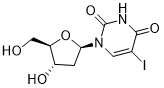

馬鞍山致研生物醫(yī)藥科技有限公司成立于馬鞍山市鄭浦港新區(qū)現(xiàn)代產(chǎn)業(yè)園。公司專(zhuān)注于生物小分子、醫(yī)藥中間體相關(guān)產(chǎn)品的研發(fā)和生產(chǎn),產(chǎn)品主要包括DNA亞磷酰胺單體、RNA亞磷酰胺單體、特殊單體以及按照客戶(hù)要求定制的RNA和DNA,并且公司提供定制合成等方面的研究服...

馬鞍山致研生物醫(yī)藥科技有限公司成立于馬鞍山市鄭浦港新區(qū)現(xiàn)代產(chǎn)業(yè)園。公司專(zhuān)注于生物小分子、醫(yī)藥中間體相關(guān)產(chǎn)品的研發(fā)和生產(chǎn),產(chǎn)品主要包括DNA亞磷酰胺單體、RNA亞磷酰胺單體、特殊單體以及按照客戶(hù)要求定制的RNA和DNA,并且公司提供定制合成等方面的研究服...